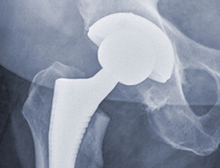

Im Wissenschaftsjahr Gesundheitsforschung soll das Augenmerk speziell auch auf diese Fragen gerichtet werden, denn schließlich geht es um alle Facetten der Gesundheitsforschung. Während die biochemische Grundlagenforschung langfristig neue Diagnose- und Therapieansätze erschließt und die klinische Forschung neue Behandlungen unter kontrollierten Bedingungen erprobt, konzentriert sich die Versorgungsforschung auf die Umsetzung im medizinischen Alltag, die „letzte Meile“ zum Patienten. Sie fragt, welcher Nutzen schlussendlich bei den Menschen ankommt.